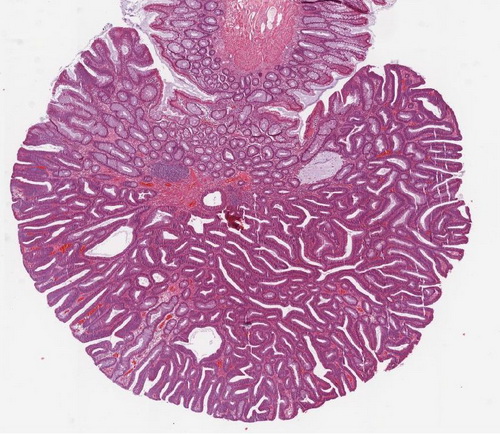

Abb. 507: Adenom bei FAP

Abb. 511: Makroskopischer Aspekt des Kolon nach Aufschneiden und Formalinfixation (in Höhe des Colon ascendens). Multiple Polypen.